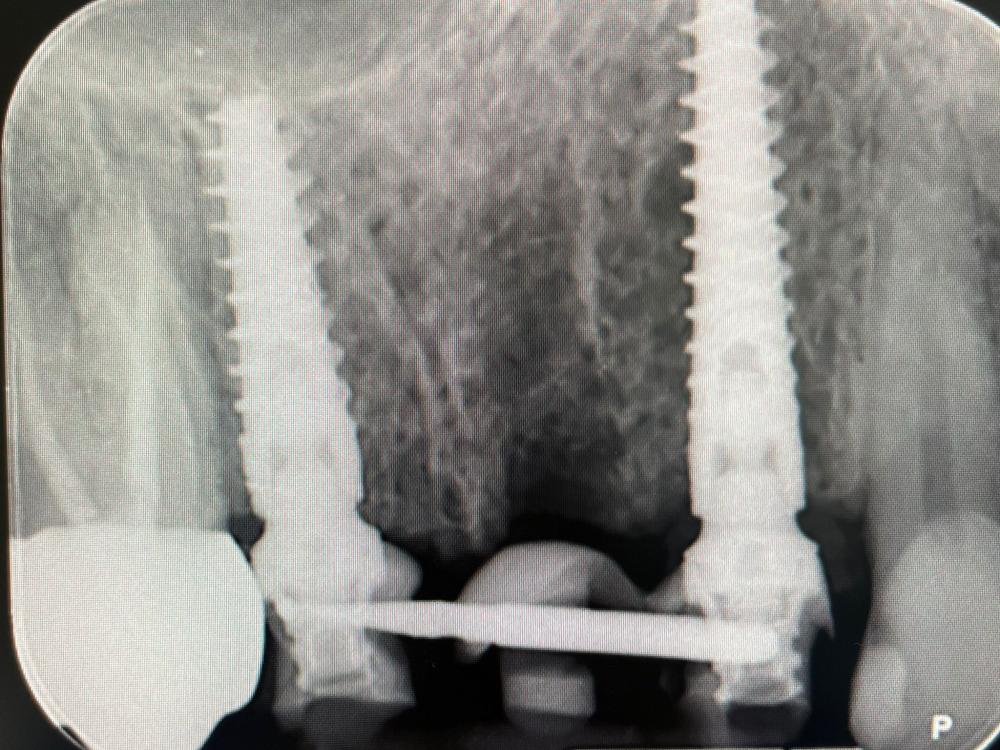

Presso lo Studio Dentistico Zambon siamo specializzati in trattamenti avanzati come il postestrattivo con carico immediato, un intervento innovativo che consente di sostituire i denti mancanti in modo rapido e sicuro, riducendo notevolmente il tempo di guarigione e il disagio per il paziente.

Grazie all’utilizzo della chirurgia guidata, siamo in grado di pianificare e realizzare impianti dentali con precisione, assicurando risultati eccellenti e duraturi.

Il trattamento postestrattivo con carico immediato è un protocollo che permette di inserire un impianto dentale subito dopo l’estrazione del dente naturale, evitando lunghi tempi di attesa tra l’estrazione e l’inserimento del nuovo dente. Questa soluzione si dimostra ideale per chi desidera ripristinare il sorriso e la funzionalità dei denti in tempi ridotti, evitando multiple sedute e massimizzando il comfort.

La chirurgia guidata è una tecnica avanzata che si avvale di tecnologie digitali per pianificare e simulare l’intervento in modo personalizzato. Con una scansione digitale 3D della bocca, il nostro team può posizionare gli impianti con estrema precisione, seguendo un percorso predefinito che riduce il margine d'errore. Questo approccio, unito al trattamento postestrattivo con carico immediato, offre diversi vantaggi: